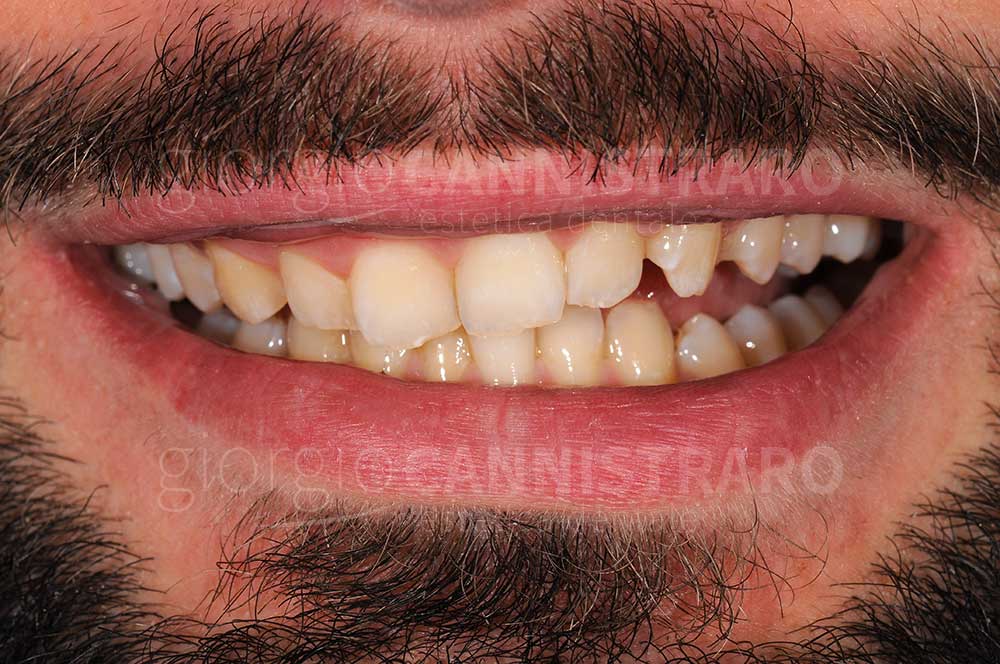

Casi di faccette in ceramica

Faccette in ceramica settore antero-superiore per eccessivo spazio tra i denti

Ragazzo 30 anni